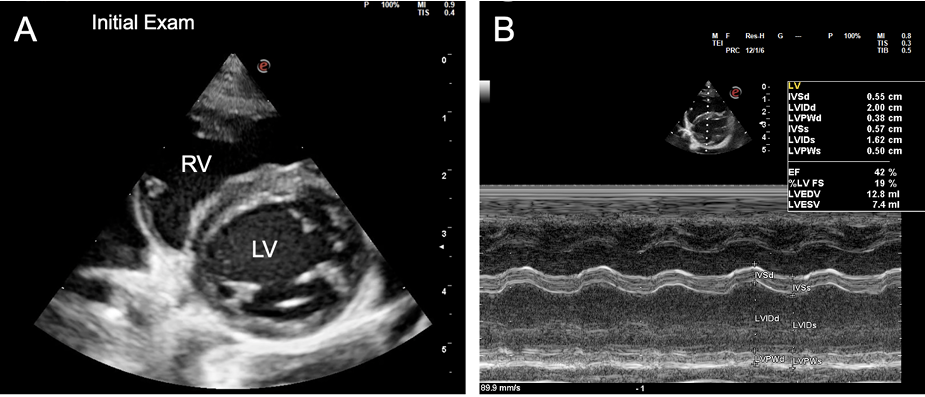

이번 연구는 1.5살의 중성화 암컷 고양이에 대한 증례 보고입니다. 해당 고양이는 이틀간의 기력 저하, 식욕 부진, 호흡 곤란 증상으로 내원하였습니다. 응급 초음파 검사에서 다량의 흉수와 소량의 복수가 확인되었고, 심장 초음파 검사를 통해 양심실 및 양심방 확장과 심수축력 저하를 특징으로 하는 확장성 심근병증(DCM) 표현형 및 울혈성 심부전이 진단되었습니다. 타우린 수치는 정상이었으며, 감염병 검사에서 Bartonella spp. 에 대한 항체(IgG)가 높게 측정되었습니다. 이에 따라 울혈성 심부전 치료(피모벤단, 푸로세마이드, 클로피도그렐)와 의심되는 바르토넬라증에 대한 항생제 치료(프라도플록사신, 독시사이클린)가 병행되었습니다.

- 초기 진단: 환자는 심각한 울혈성 심부전 상태였으며, 심장 초음파 검사상 심장이 전반적으로 확장되고 수축 기능이 현저히 저하된 전형적인 DCM의 모습을 보였습니다.